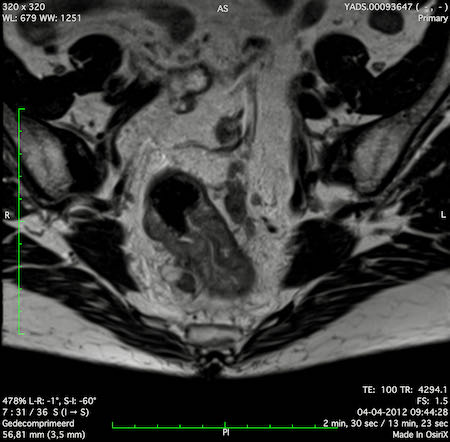

Hình ảnh

Các hình ảnh được cung cấp cho thấy ung thư biểu mô tế bào nhẫn với tình trạng dày lan tỏa thành trực tràng, hình ảnh bia bắn điển hình, và sự xâm lấn mỡ mạc treo trực tràng.